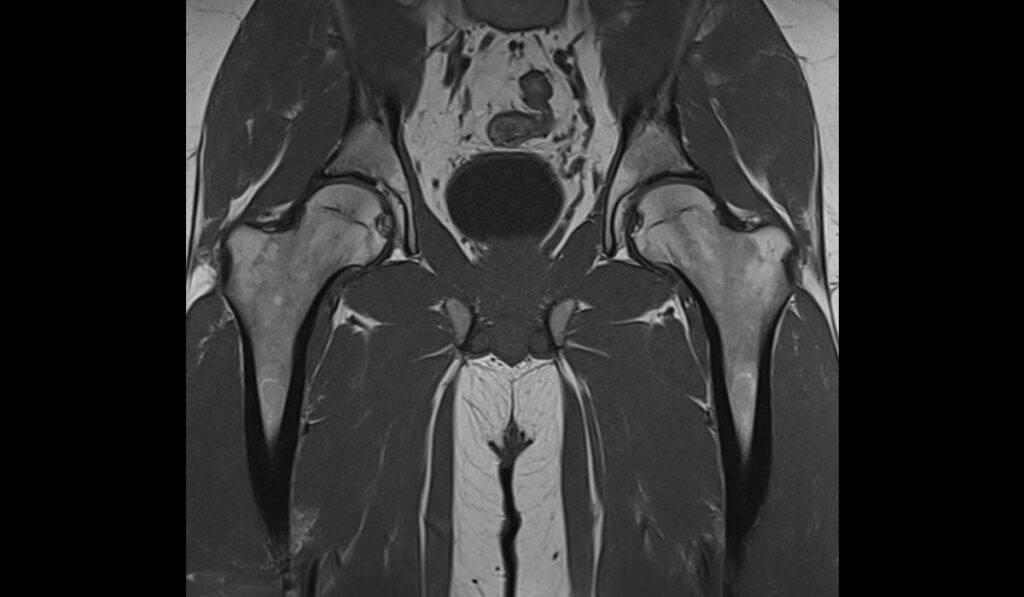

Was man bei der MRT Untersuchung der Hüfte sehen kann

Mit Hilfe der MRT Untersuchungen lassen sich Strukturen im Bereich der Hüfte darstellen, die mit einem Nativröntgen gar nicht oder nur unzureichend darstellbar sind. Im Folgenden werden die zwei häufigsten Erkrankungen sowie ihre Merkmale in der MRT aufgeführt.

Arthrose

Bei der Arthrose können insbesondere die Begleitveränderungen gut dargestellt werden. Dazu zählen: ein möglicher Gelenkerguss (vermehrte Ansammlung von Flüssigkeit im Gelenk), subchrondrale Zysten (flüssigkeitsgefüllter Hohlraum unterhalb des Knorpels), ein Stressknochenmarködem (vermehrte Flüssigkeitsansammlung), eine reaktive Synovitis (entzündlicher Prozess, Ansammlung von Flüssigkeit) oder ein reaktives Knochenmarködem (Flüssigkeitsansammlung, dargestellt als weiße Flecken).

Diese Begleitveränderungen zählen bei der aktivierten Arthrose zu den häufigsten Ursachen für die akuten Schmerzen.

Wichtig ist in diesem Zusammenhang jedoch, dass die Veränderungen auch bei anderen Erkrankungen auftreten können. Eine Differentialdiagnose zur Abgrenzung von der rheumatoiden Arthritis, posttraumatischen Läsionen oder einer rapid-destruktiven Osteoarthrose ist daher von Nöten.